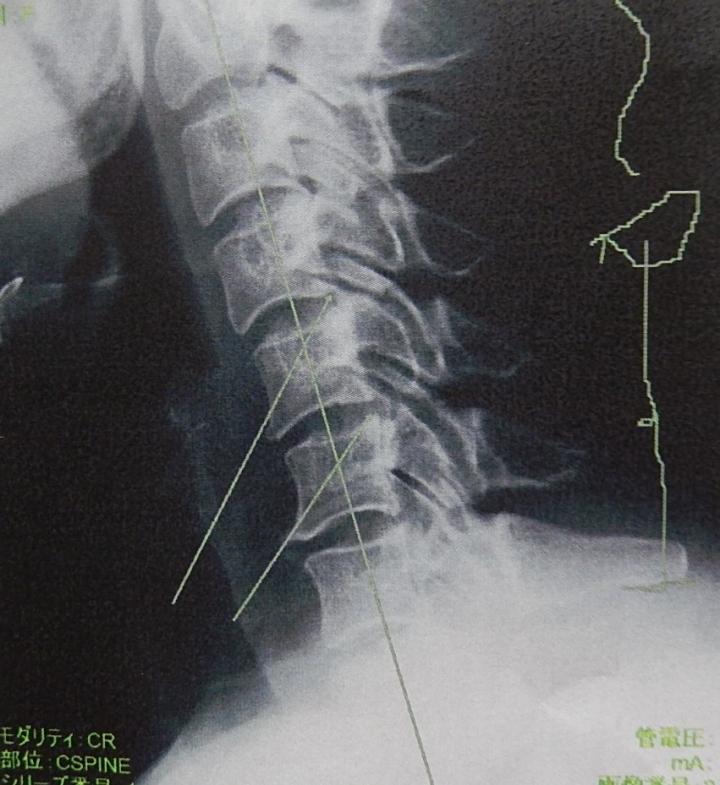

じゃじゃ~ん🎶 これ、管理人の首~~~~~(*'▽')

見事な「ストレートネック」!

重い頭を支えきれない首になってしも~た~!

首は曲がっていないといけないそうで、2本の矢印の先に負担がかかってしびれている~。